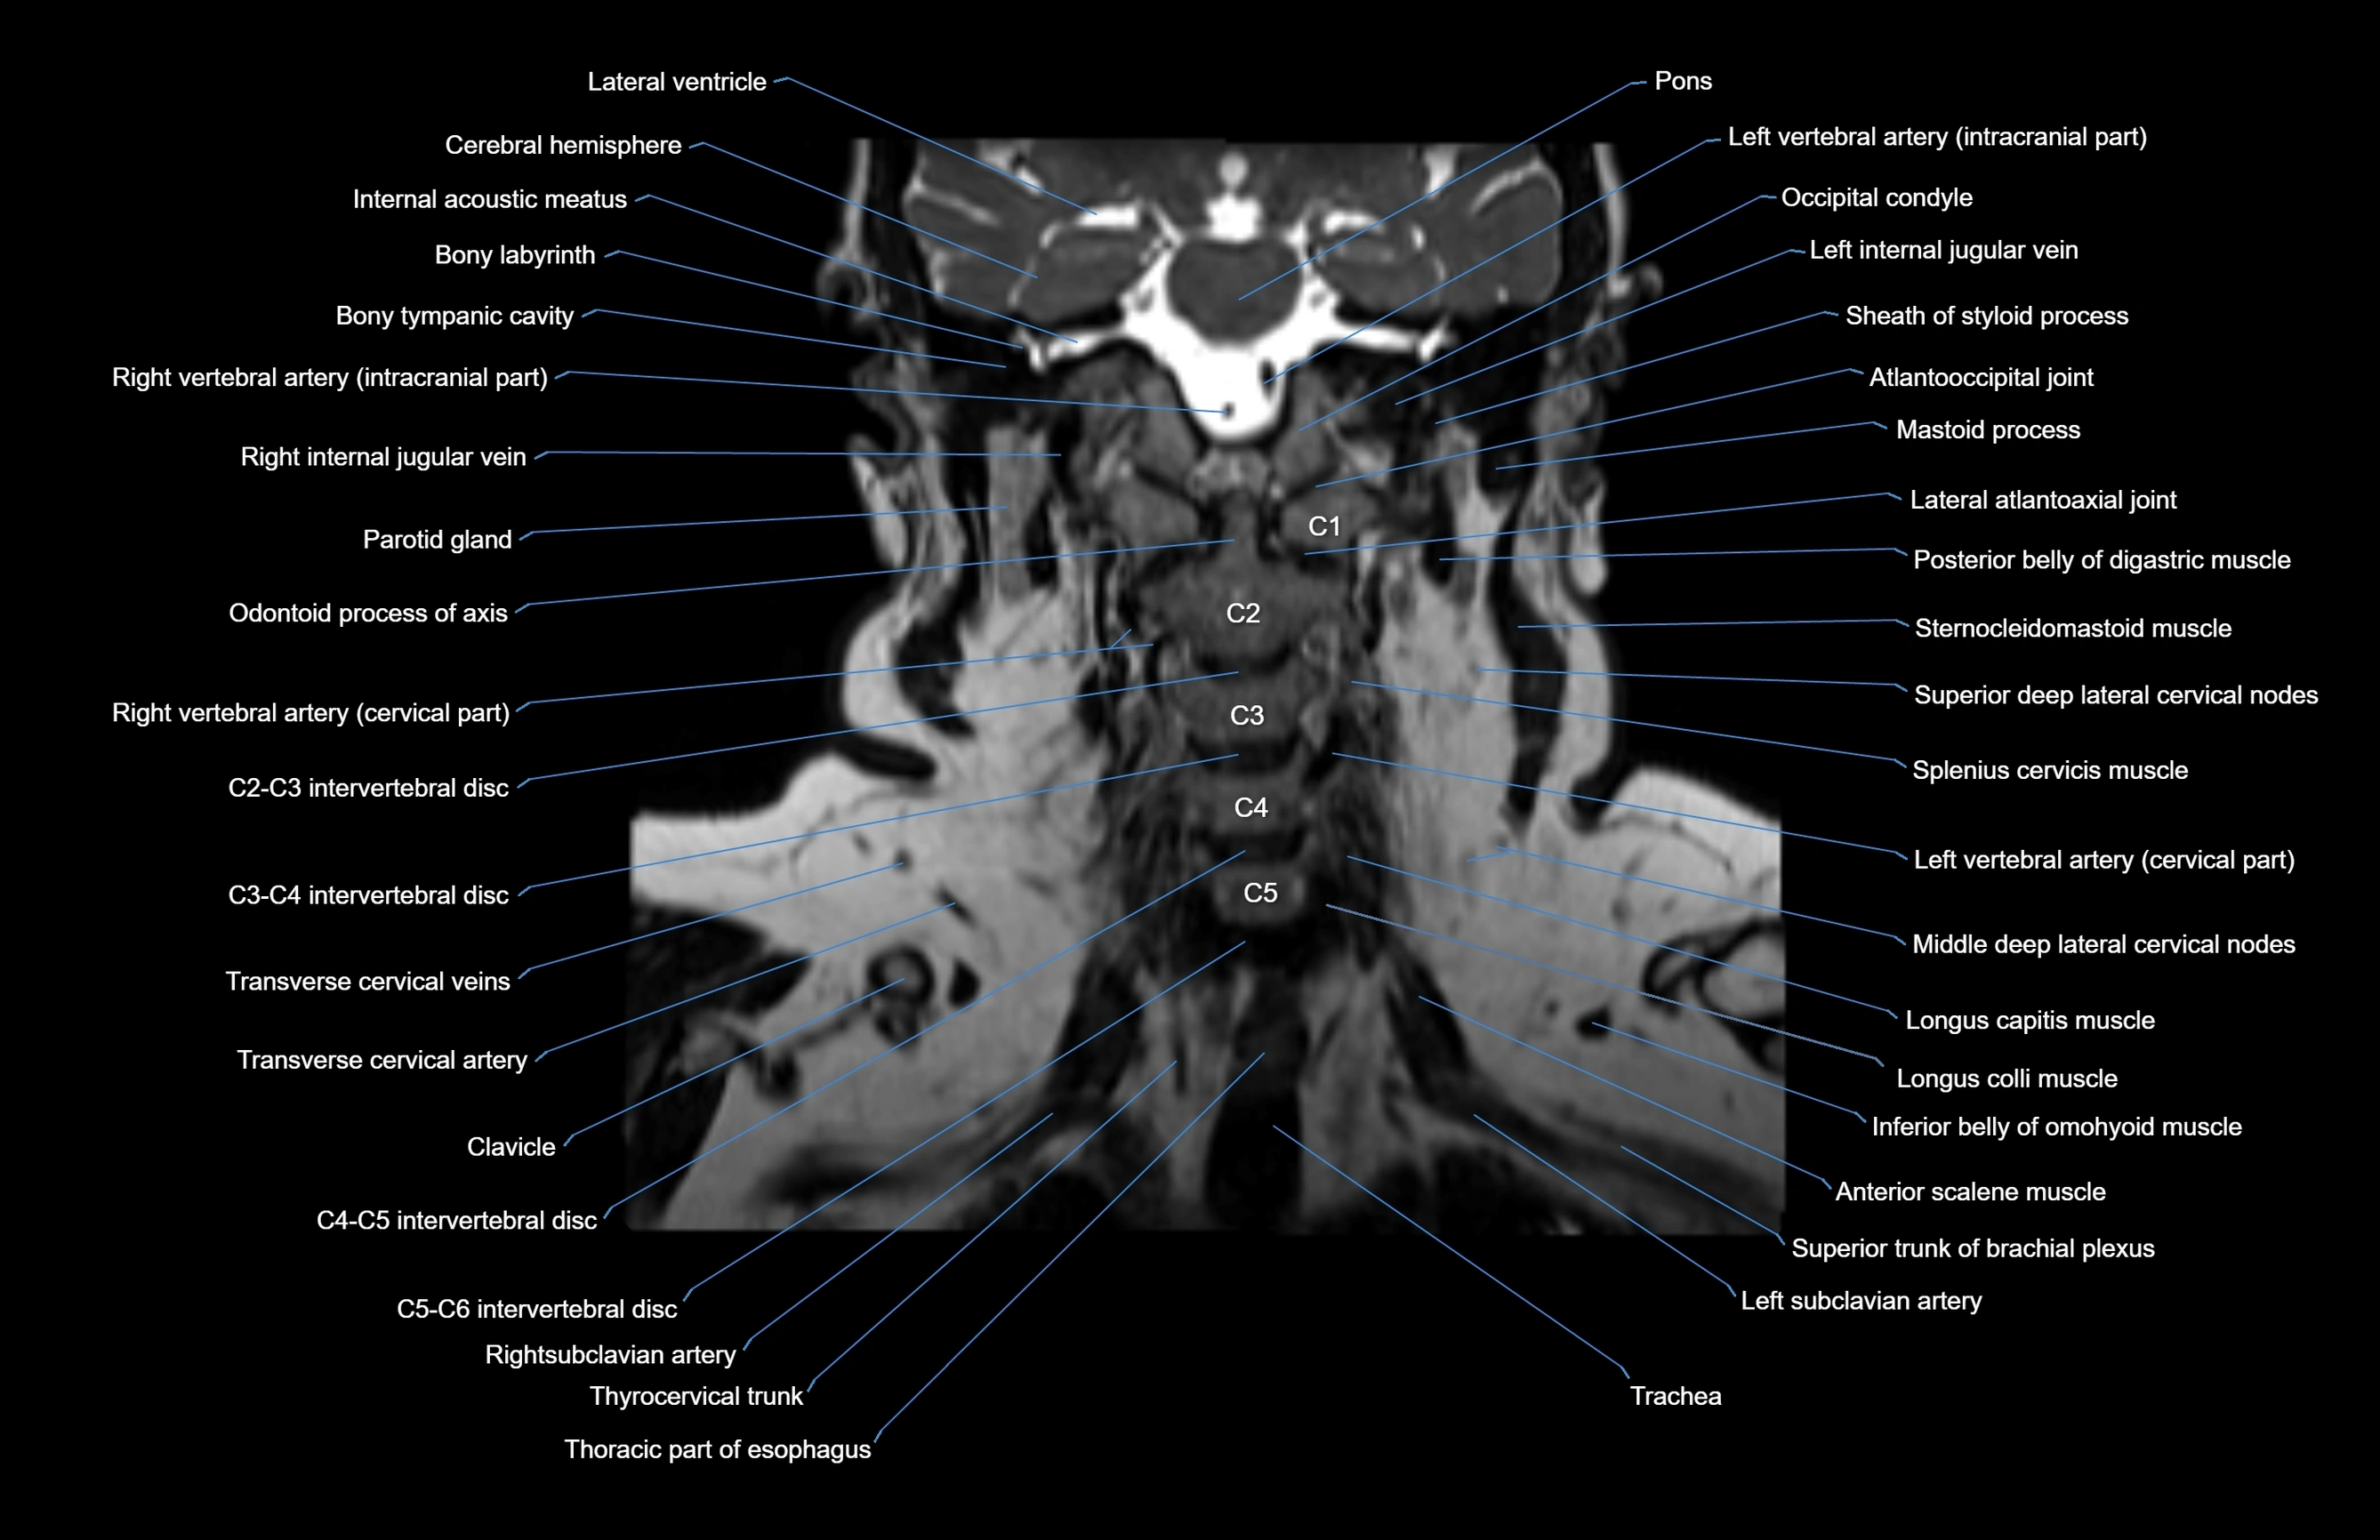

- Atlantooccipital joint

- Cervical spinal nerve 1 (C1)

- Cervical spinal nerve 2 (C2)

- Cervical spinal nerve 3 (C3)

- Cervical spinal nerve 4 (C4)

- Cervical spinal nerve 5 (C5)

- Left Vertebral Artery (Intracranial Part)

- Left vertebral artery (atlantic part)

- Left vertebral artery (cervical part)

- Occipital condyle

- Right Vertebral Artery (Intracranial Part)

- Right vertebral artery (atlantic part)

- Right vertebral artery (cervical part)